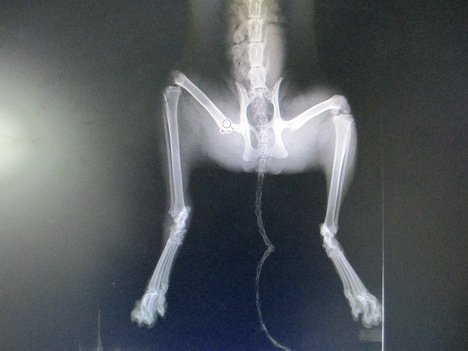

主題: 疑似被咬傷的玳瑁母貓 申請者姓名: 敏大哥 花色: 申請日期: 2012-05-09 16:38:47 申請者部落格: 申請者臉書網址: 所在縣市/合作醫院: 台北市/欣旺動物醫院 治療費用: 6300元 需求人數: 8人 已結案 (2012-11-25 22:06:48) 報名人員: suxiwen(已付款)、suxiwen(已付款)、張拉可(已付款)、Weirong(已付款)、嘟嘟(已付款)、嘟嘟(已付款)、孫潤晨(已付款)、徐雅嬪(已付款)、 候補人員: 盧靜儀、小舟、 動物病情說明: 4/15網友通報在南港輪胎附近.有1隻疑似3隻腳的貓蹲在輪胎下.看起來很痛苦.都不離開.給牠吃食物也不吃.由我去救援回來就醫.到醫院檢查之後.發現右後之腫脹頗足.經由x光檢查確定沒有骨折.有可能是被咬傷造成傷口嚴重感染.導致於貓咪無法行走.

經過治療之後帳款結算到4/29療程結束.從4/30到5/8號愛媽不放心自費留至醫院觀察.目前愛媽帶回照顧中.等完全康復會R回原地